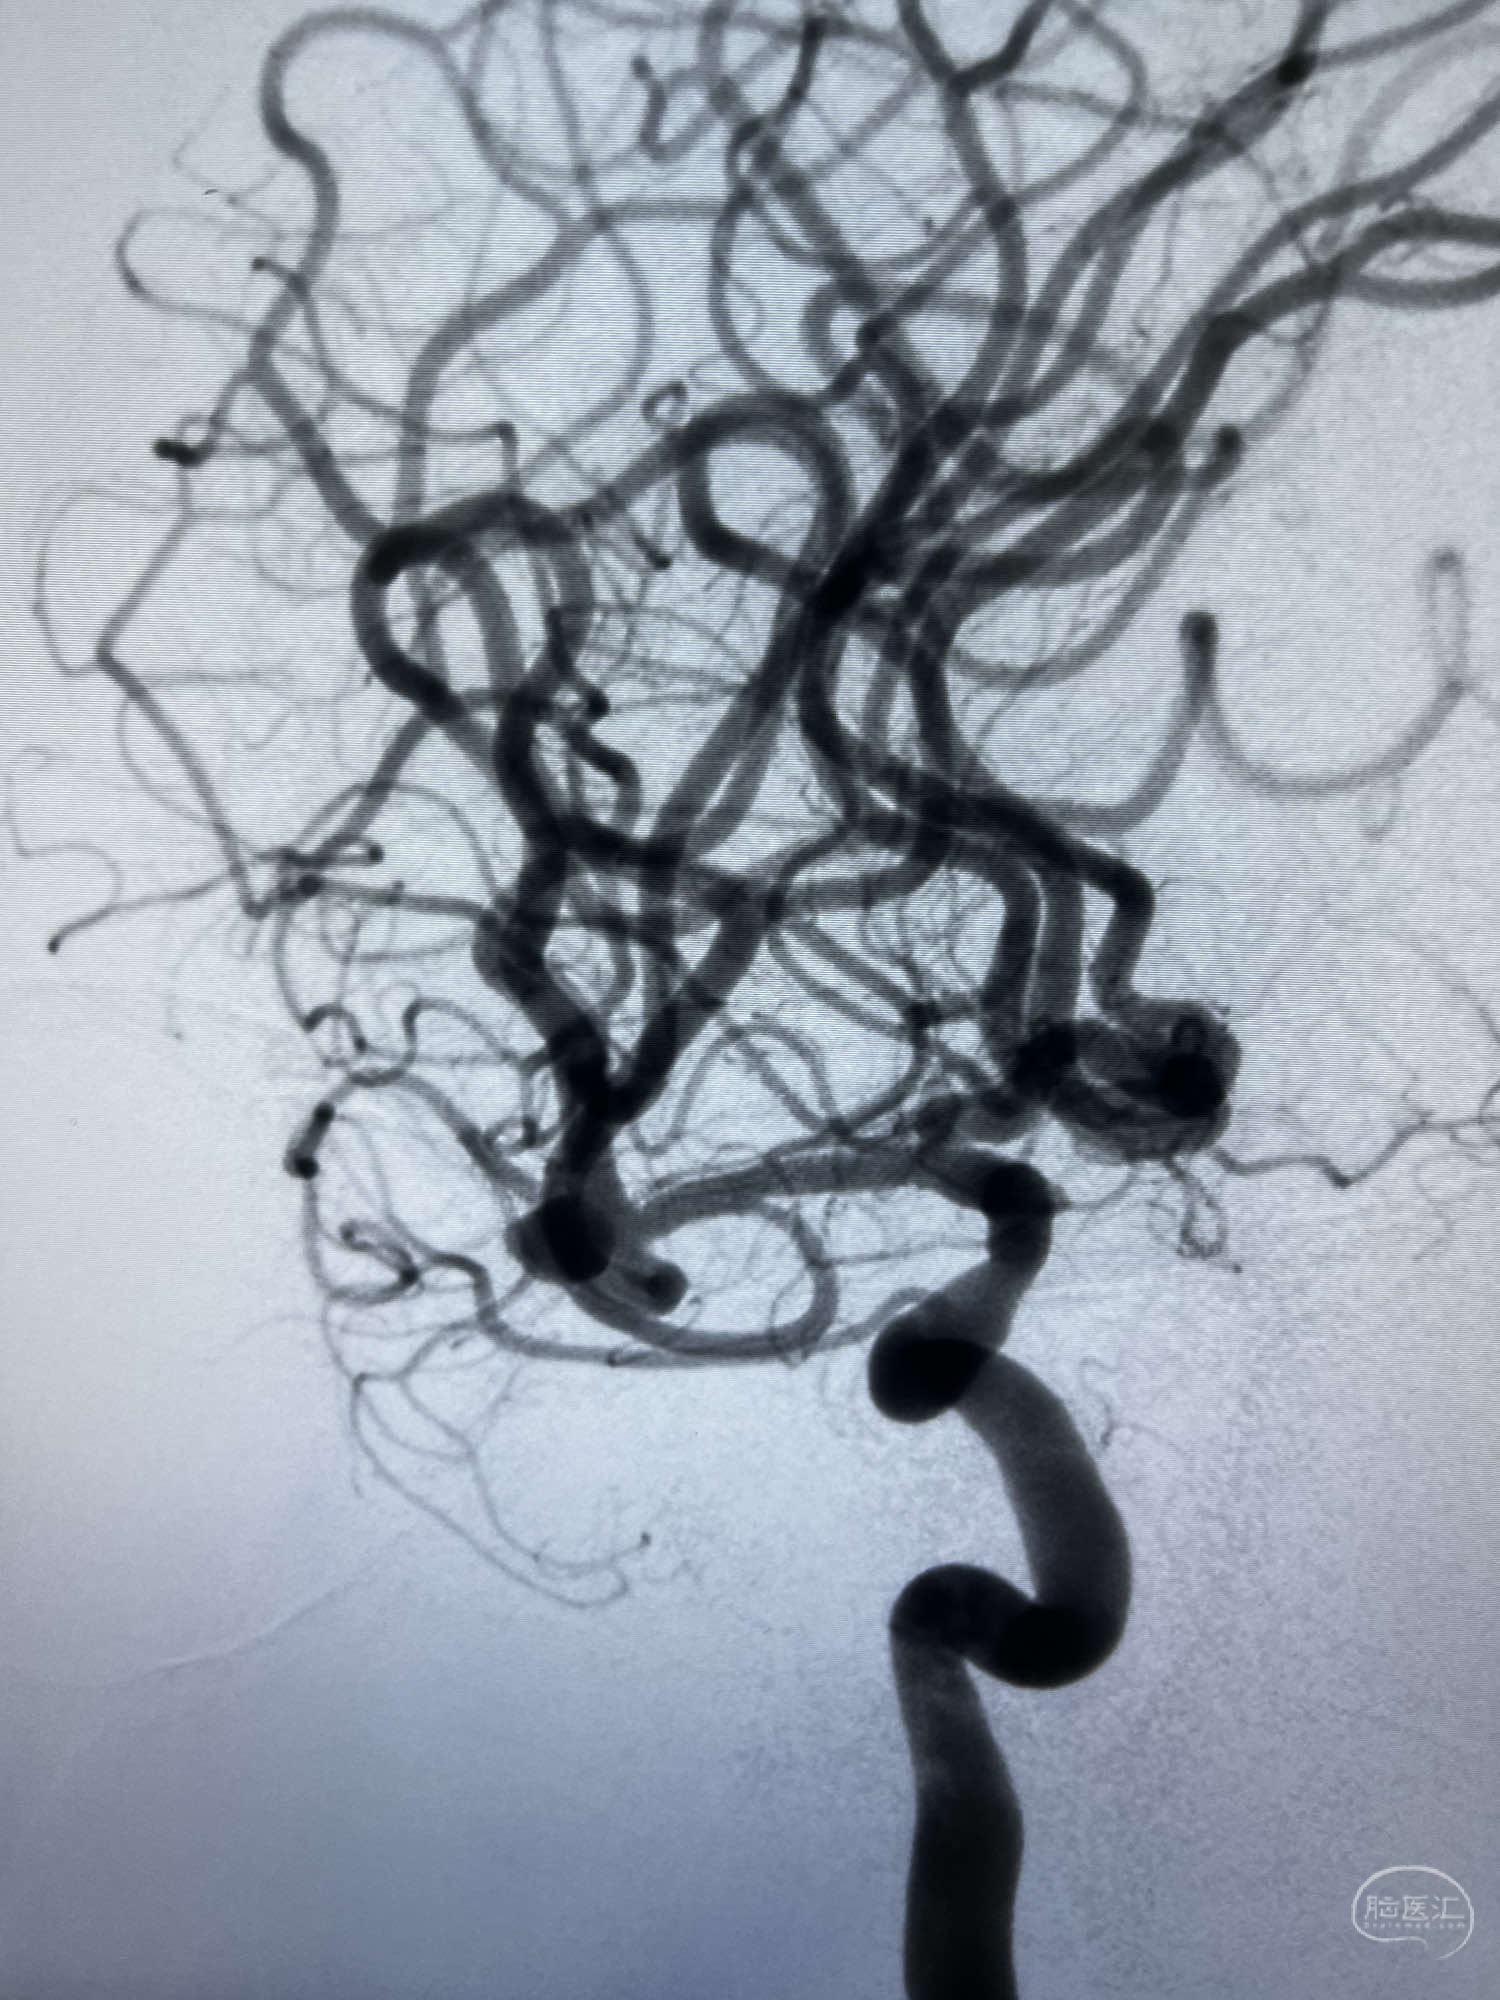

6F Neuromax➕6F115cm 心玮中间导管建立路径,sychro14微导丝➕VIA21超选至动脉瘤体内近中部,WEB5mmx3mm植入动脉瘤。

WEB瘤内扰流装置5mmx3mm经过“种子、萌芽、开花”三个阶段,打开后良好贴壁,动脉瘤内血液滞留,载瘤动脉通畅。WEB一步到位,通过瘤内扰流的方式起到栓塞动脉瘤的作用,避免了应用支架保护分支血管,简化了操作步骤,降低了术中血栓及出血的风险。